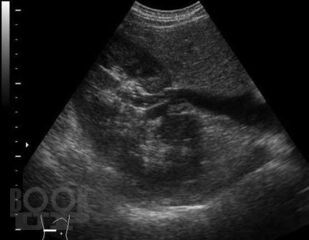

В основу монографии положены результаты собственных исследований и практический опыт авторов, использования ультразвуковых методов исследования мочевыделительной системы у тяжелой группы пациентов в промежуточном и позднем периодах позвоночно-спинальной травмы, проанализированы литературные данные отечественных и зарубежных авторов.

В монографии представлены современные методы комплексного ультразвукового исследования и патологические изменения мочевыделительной системы при позвоночно-спинальной травме. Описаны ультразвуковые симптомы поражения почек и верхних мочевых путей. Представлена разработанная авторами, эхосемиотика нейрогенного мочевого пузыря и эхосемиотика предстательной железы при позвоночно-спинальной травме. Описана технология проведения ультразвукового исследования у прикованных к постели и коляске, нуждающихся в постоянном постороннем уходе больных с последствиями позвоночно-спинальной травмы. Динамическое комплексное ультразвуковое исследование мочевыделительной системы позволяет осуществлять диагностику, мониторинг лечения и оценивать своевременность и эффективность урологического пособия пациентам, перенесшим позвоночно-спинальную травму.